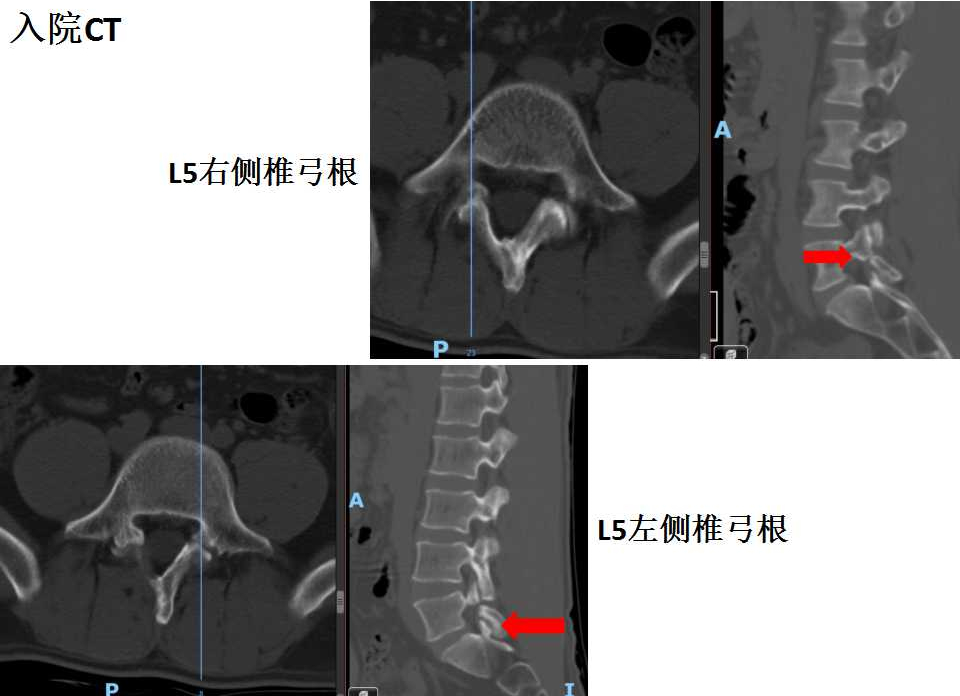

腰椎CT示双侧峡部裂